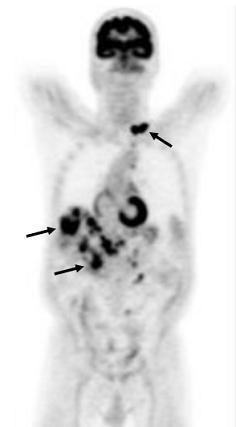

PET图像 能敏感显肿瘤及转移病灶(黑箭),但组织器官的轮廓结构显示不良